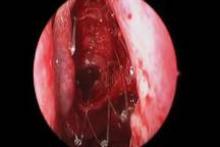

Photo courtesy Intersect ENT

The photo above shows polyps obstructing the ethmoid sinus before surgery.